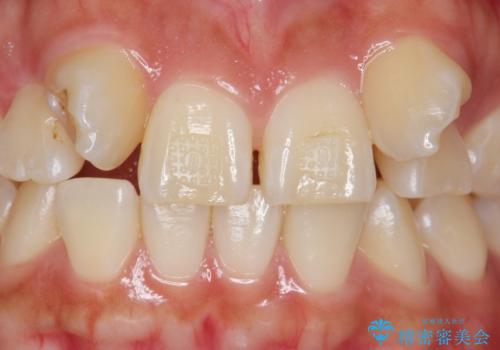

- 生まれつき上の側切歯と犬歯が逆に生えていることを主訴に来院された患者様です。

他院で矯正を行っていたそうですが、なかなか終わらないため途中で治療をやめてしまったとのことでした。

矯正以外の治療法で早く治したいとのご希望により、上顎両側犬歯を抜去しオールセラミックのブリッジによる補綴治療を行いました。